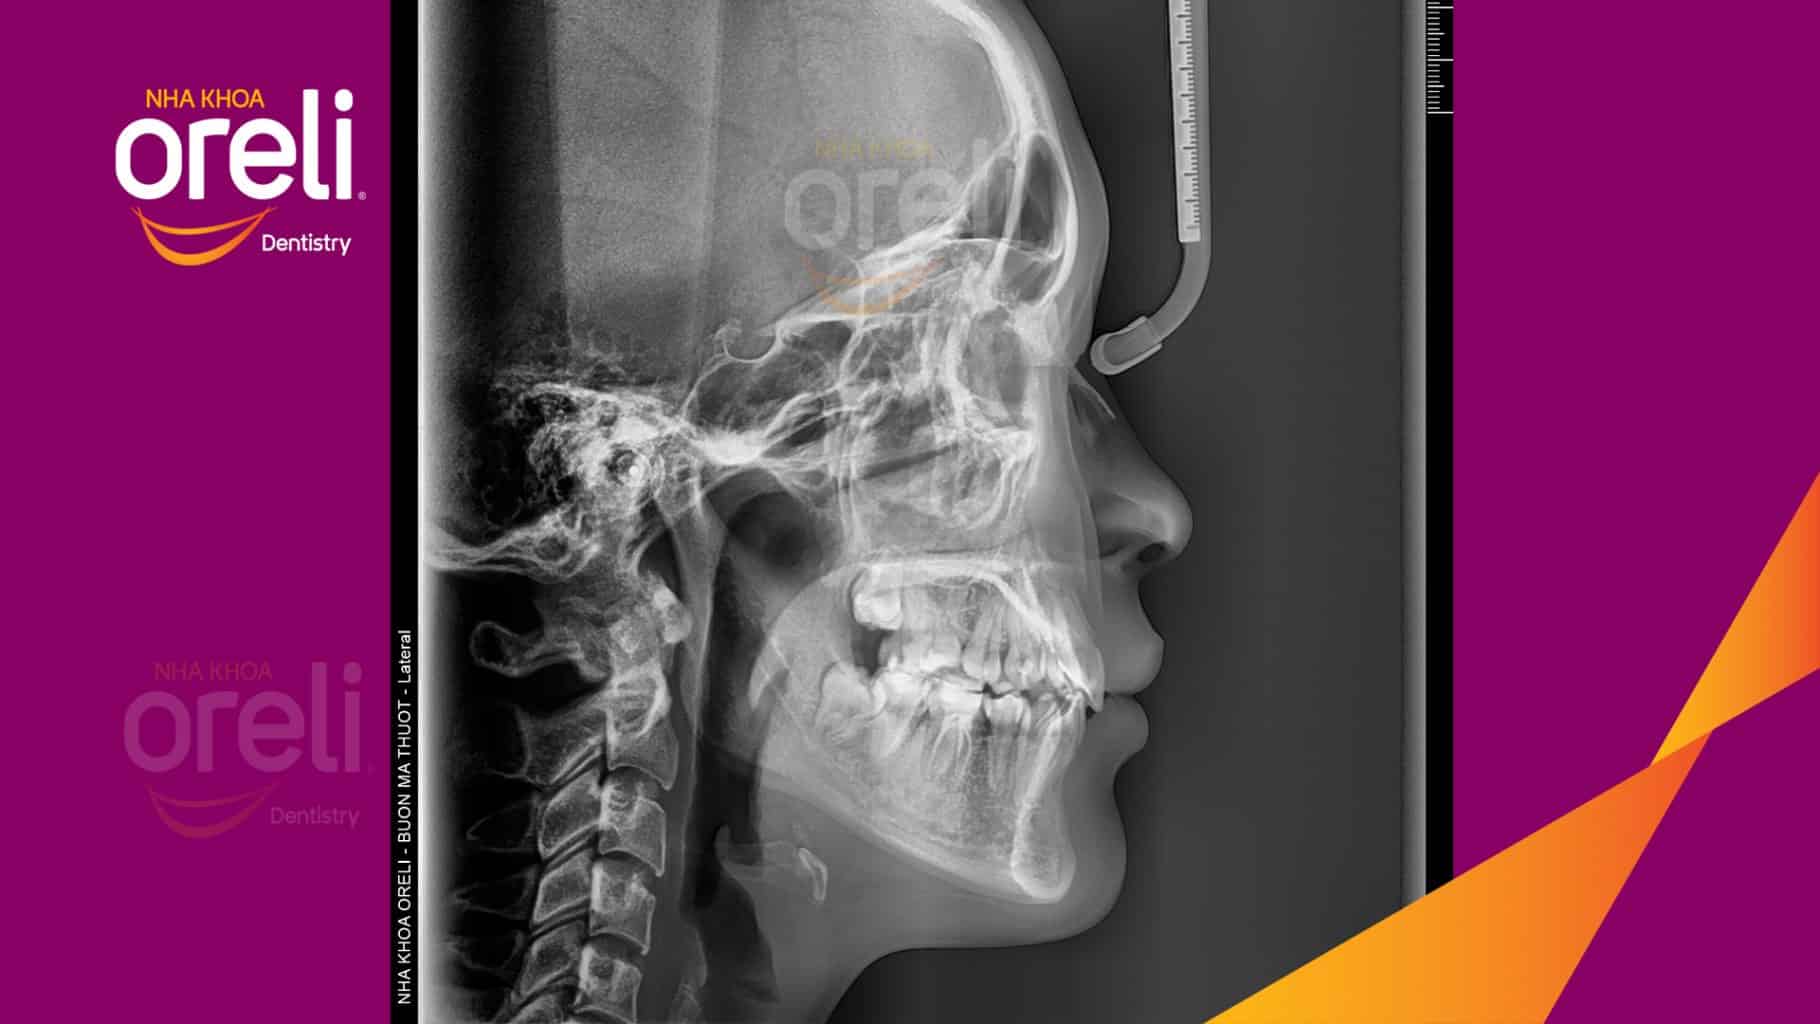

Tình trạng: Nhô xương ổ, trục răng nghiêng trước hai hàm, độ nhô môi nhiều

Giải pháp: Nhổ răng 4 chỉnh hô

Thời gian: 24 tháng

Kết quả: Nụ cười hài hòa, mặt nghiêng đẹp, trục răng cửa đứng